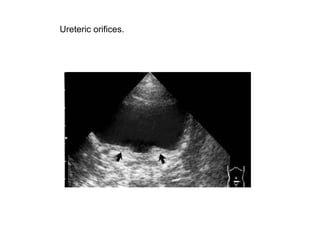

Ureteric orifices.